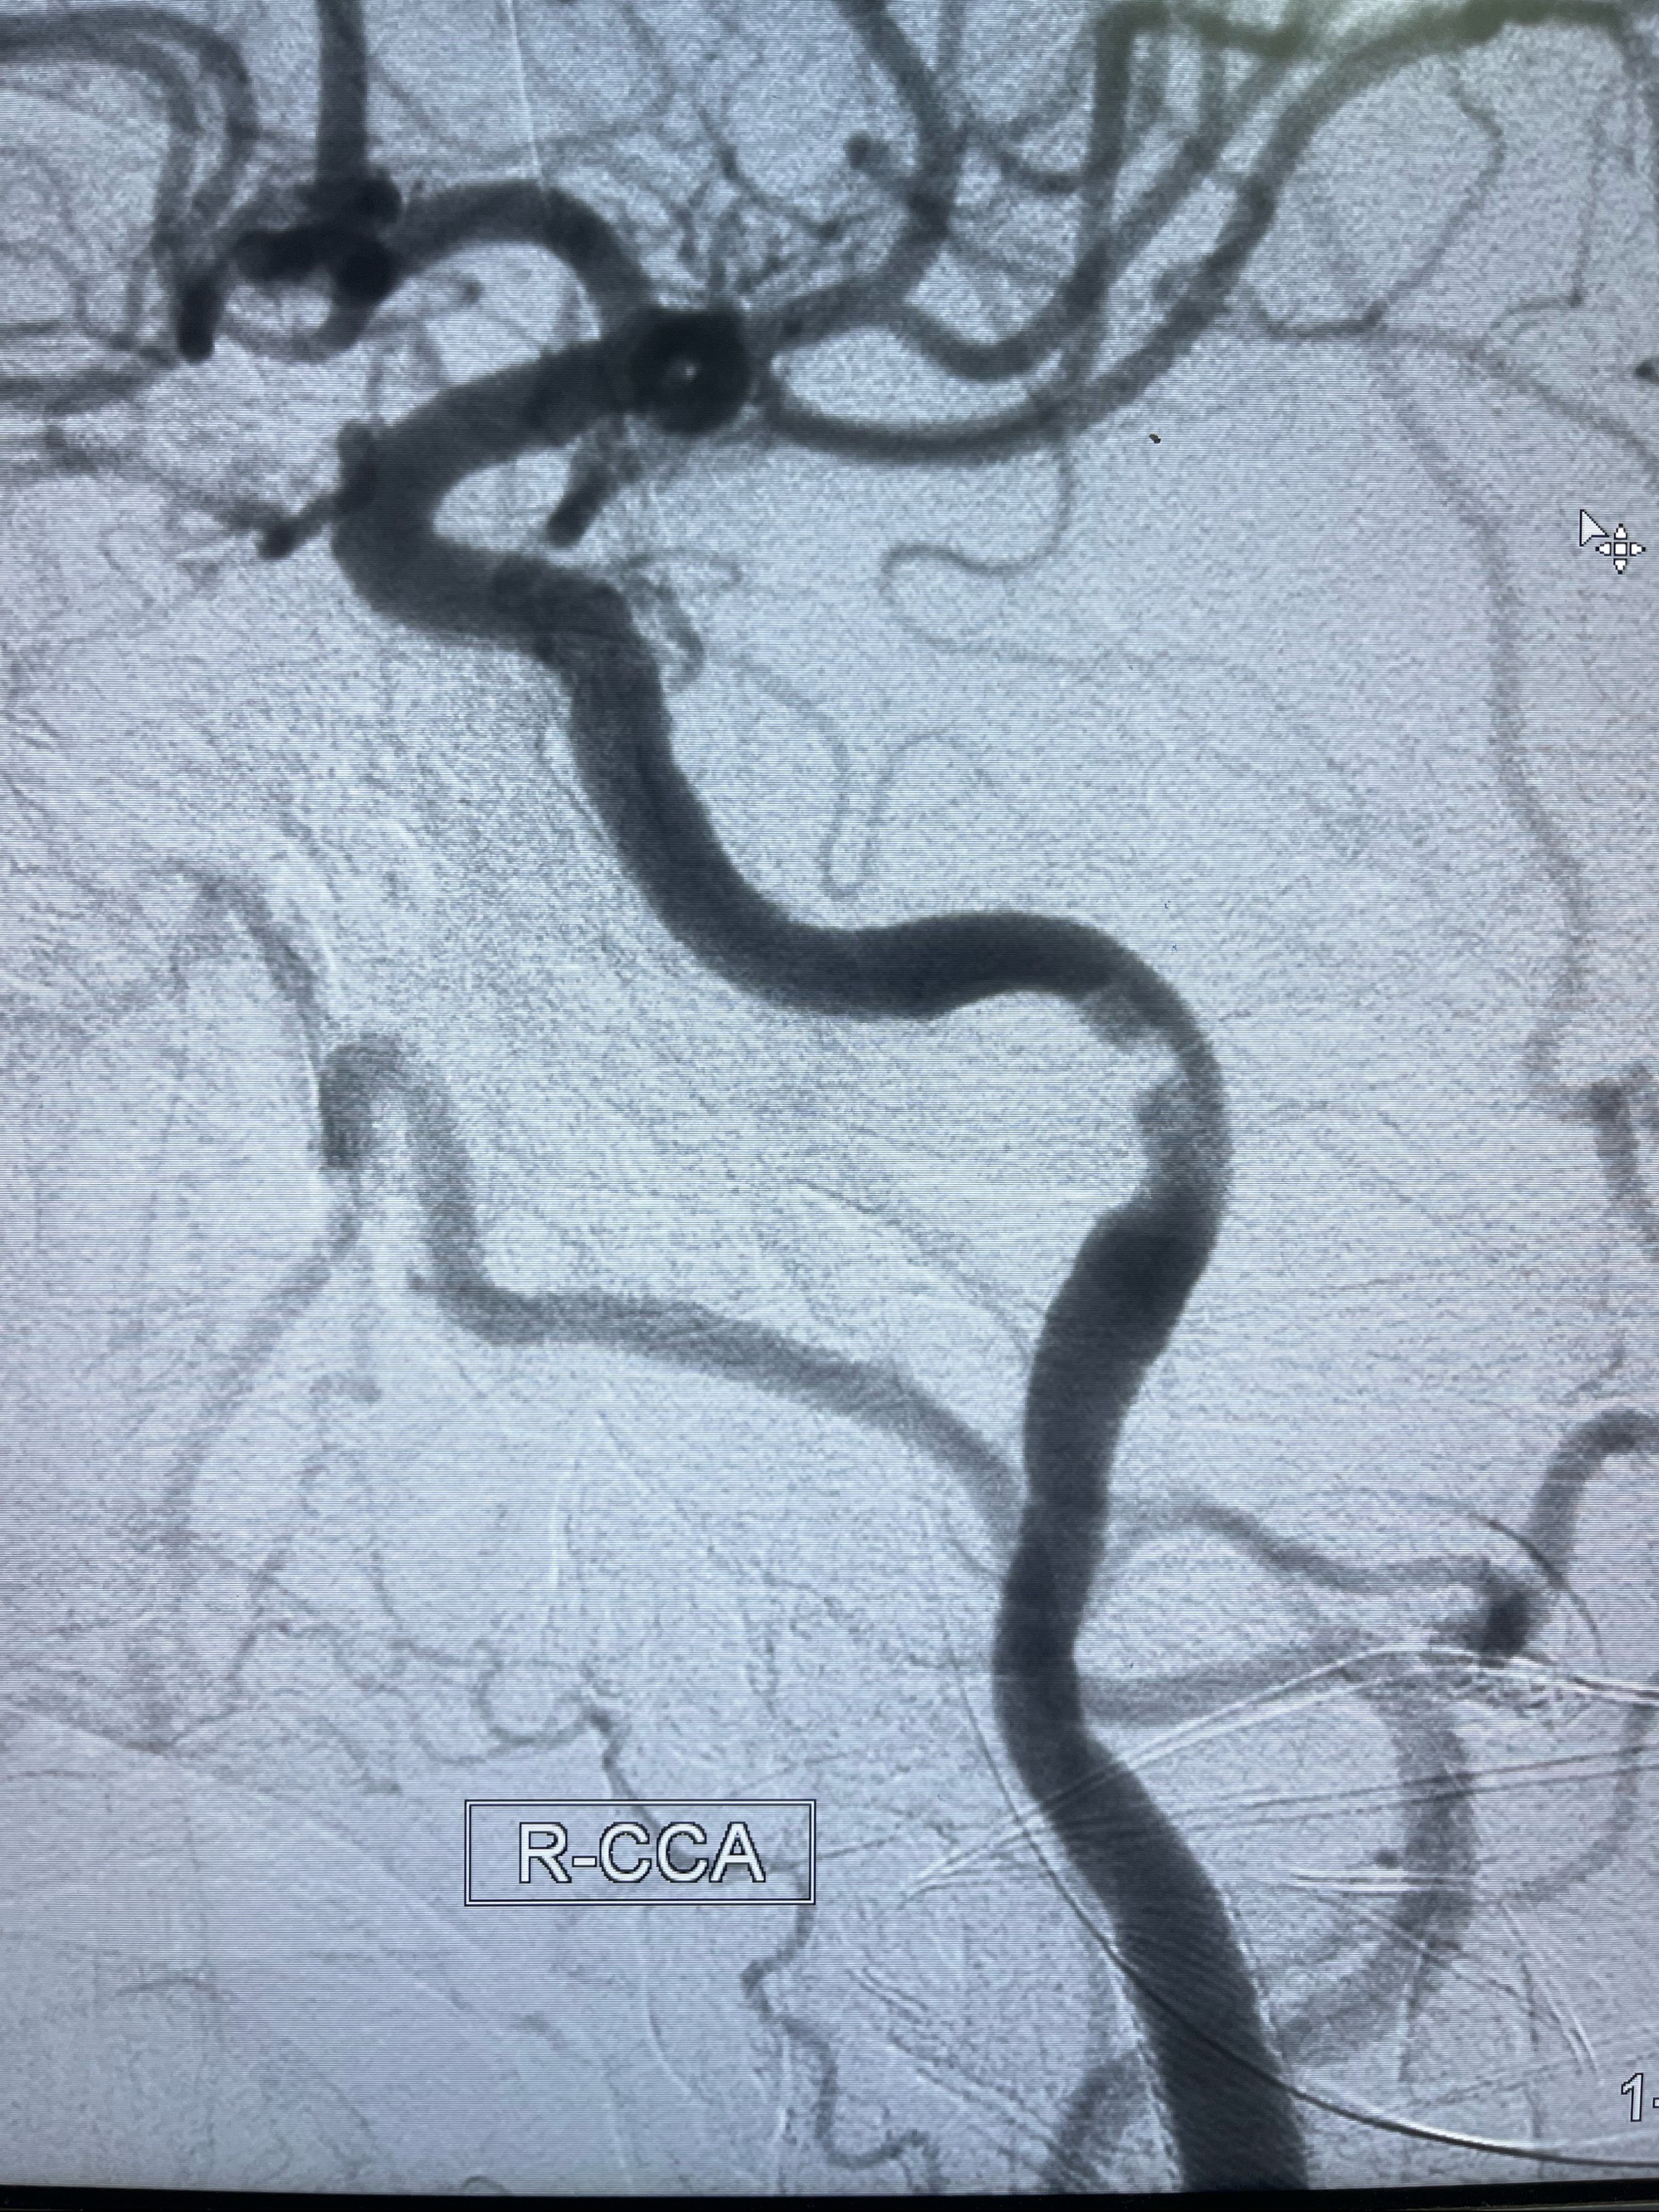

2023-07-10DSA:右侧颈内动脉岩骨段夹层伴中偏重度狭窄改变,左侧颈总动脉闭塞、右侧颈外动脉由右侧肋颈干甲颈干吻合代偿

箭头所示为颈内动脉岩骨段重度狭窄,结合MRI,考虑为肿瘤侵犯右侧颈内动脉

箭头以近至支架段管腔不规则狭窄

MRI:显示肿瘤侵犯右侧颈内动脉岩骨段上下,向下至原颈内动脉支架远心段,向上至颅底